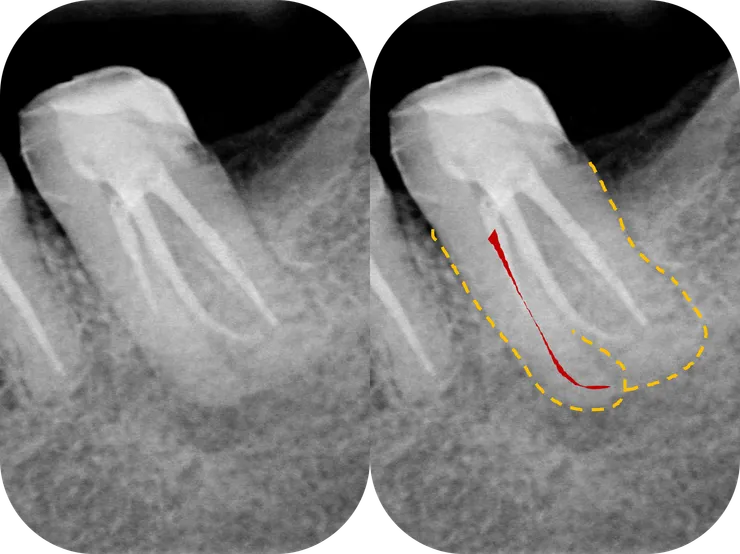

如同開場白強調的,任何 case 在開始前,務必、千萬、一定要先看清楚 root form (橘色虛線) & canal path (紅線)!

就算 canal 鈣化到看不到,也可以依據 root form 來推測出 canal 可能的走向。

如右圖所示,從依據 root form 推測出的 canal path 看來,原本的路徑似乎偏移不大,是不是繼續往下鑽就可以了呢?

可是前一位是認真的 endo 專ㄟ!事情有那麼簡單嗎?